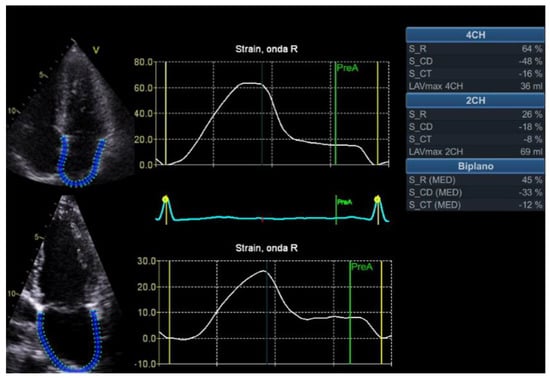

2. Global Longitudinal Strain

2.1.2. HFpEF